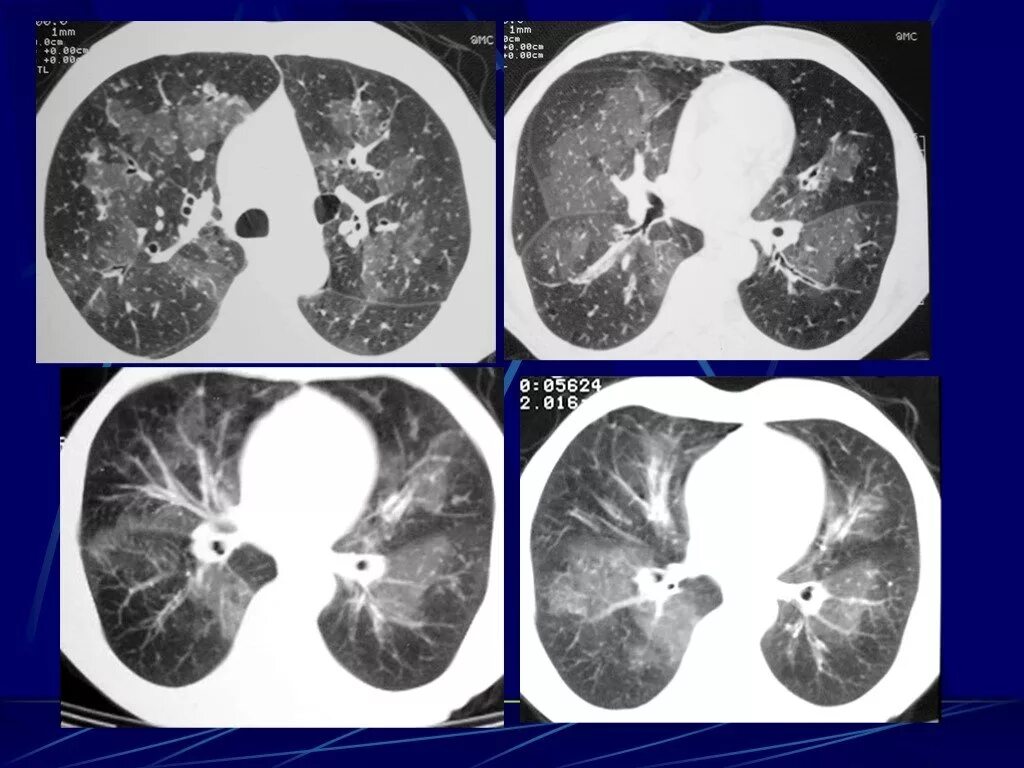

Гипостатические изменения кт